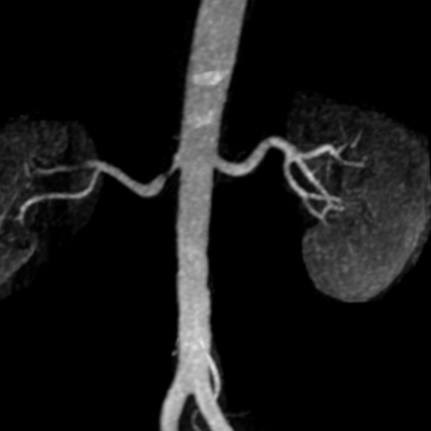

За първи път в УМБАЛ „Канев“ беше извършено безкръвно лечение на вазоренална хипертония. Това е състояние, при което високото кръвно налягане се дължи на стеснение на бъбречна артерия.

Съдовият хирург д-р Стоян Генадиев, дм, сподели, че пациентката, която е само на 48 години, поддържала кръвно налягане над 180/100 мм/Жв, въпреки приемът на три антихипертензивни медикамента в максималната им доза.

Д-р Генадиев обясни, че този тип процедури не изискват обща анестезия, няма оперативни разрези, пациентите се раздвижват шест часа след процедурата и няколко дни по-късно могат да се върнат към нормалния си начин на живот. Днес пациентката беше изписана от отделението с кръвно налягане 120/90 мм/Жв, без да се налага да приема лекарства.